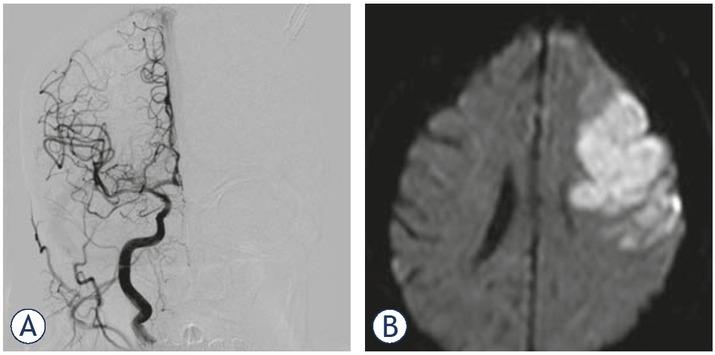

Conventional (digital subtraction) angiography confirmed right MCA occlusion with good collateral flow provided by the right anterior cerebral artery (ACA). However, the situation on the left side had changed. Namely, a complete recanalization of the carotid “T” occlusion was seen angiographically as a consequence of thrombolysis and distal migration of the thrombembolus (now presenting with proximal M2 segment occlusion of the major MCA branch). However, no collateral flow was observed despite complete left ACA patency (Figure 3). Endovascular mechanical recanalization with aspiration was successfully performed on the right side (Figure 4A). The same procedure was not performed on the left side because there was irreversible brain damage in the whole occluded arterial territory and a high risk of haemorrhagic complications. The postprocedural thrombolysis in cerebral infarction (TICI) scores were 3 (right MCA) and 2b (left MCA).

(A) Digital subtraction angiography (DSA) after mechanical recanalization. Right M1 mechanical recanalization (aspiration device) led to complete flow restoration. (B) MR diffusion weighted imaging (DWI) scan taken 6 days after mechanical recanalization: complete salvage of the affected right middle cerebral artery (MCA) brain parenchyma (recanalization at 7 hours after stroke onset). In contrast, subsequent persistent left M2 occlusion without collateral flow resulted in significant stroke within 3 hours after stroke onset.

The control CT and magnetic resonance imaging (MRI) scans performed on the next and subsequent days revealed no ischaemic damage on the right side and acute ischaemic stroke in the corresponding left MCA territory (Figure 4B). The patient was discharged with an improved clinical condition. However, severe neurological deficits (global dysphasia, dysarthria, spastic hemiplegia of the right limbs) were a consequence of permanent brain damage on the left side (NIHSS 5, mRS 5).